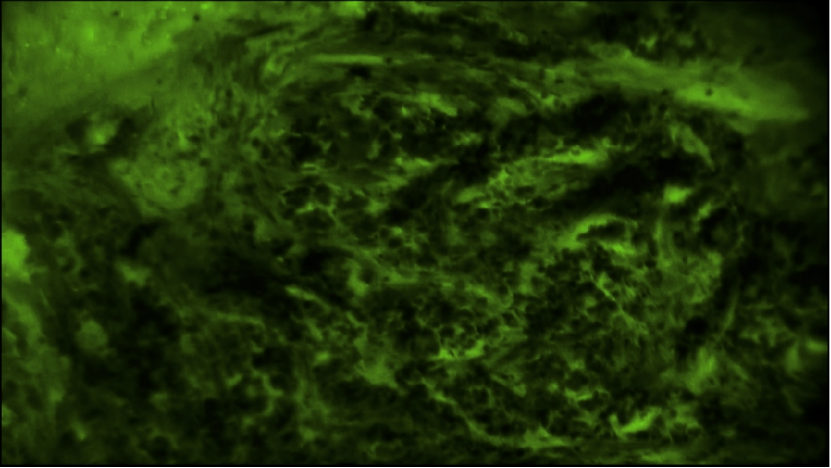

EndoSCell?鏡下常見(jiàn)的乳腺浸潤(rùn)性癌腫瘤細(xì)胞圖像:細(xì)胞核大大小小且密度很高